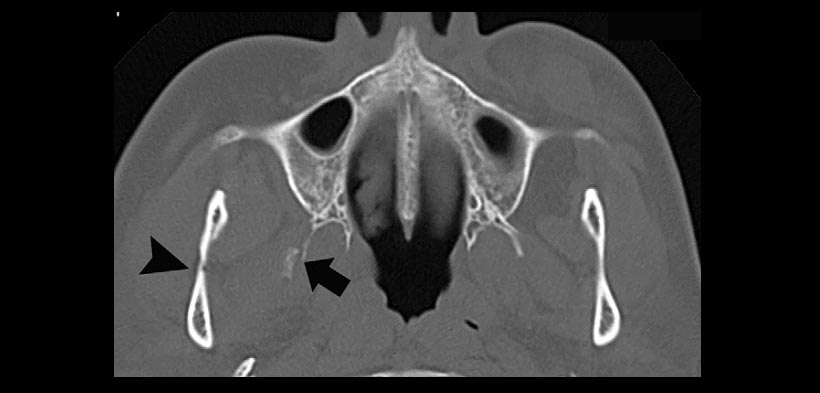

Figura 1. Fracturas típicas mandibulares con desplazamiento acompañado de una fractura del maxilar posterior en un paciente de 64 años de edad que sufrió una caída de escalera. Esto muestra las fracturas de la placa pterigoides, placa lateral (flecha) y de la mandíbula (punta de flecha).